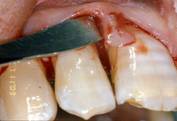

• PPD (periodontal pocket depth) [fig. 2];

•  Fig 2

Initial probing

• R: gingival recession, i.e. the position of the gingival margin with respect to the cement enamel junction (CEJ);

• CAL (clinical attachment level): i.e. the position of the attachment in relationship to the CEJ;

• IBPD (intrabony pocket depth): distance between the CEJ and the bone crest.

Periodontal pockets were measured with a manual probe marked in millimiter increments. Bleeding on probing was recorded and the presence of plaque was registred mesially, buccally, distally, and lingually. Data were obtained at baseline before treatment and at 10 days, and 6,9, and 24 months after treatment.